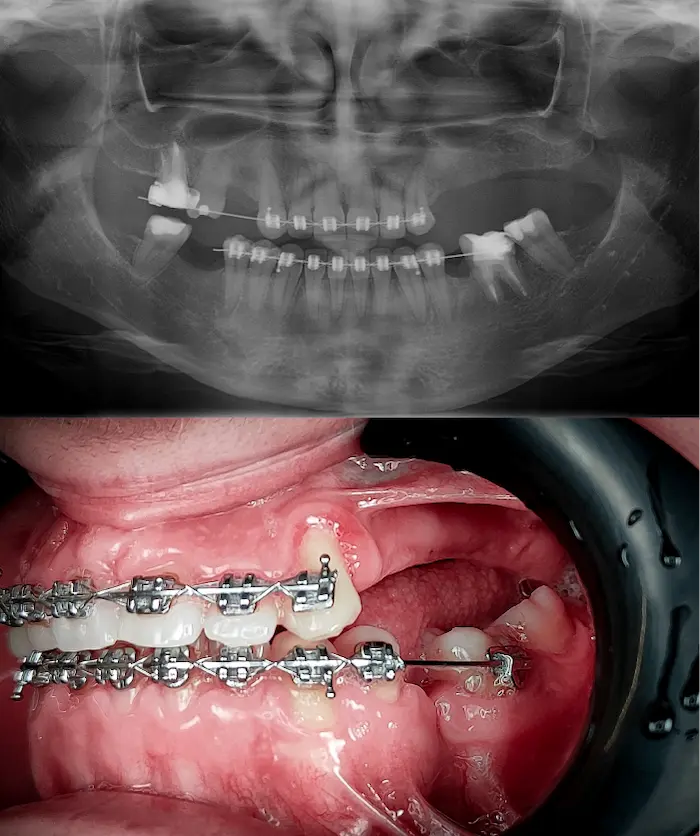

Durante la prima visita valutiamo se sei un candidato per impianti All-on, impianti zigomatici o impianti subperiostali.

Prima visita diagnostica completa gratuita*

Esame clinico, radiografia panoramica 2D e scansione CBCT 3D.

Analisi dello stato osseo

Se l’osso non soddisfa i criteri per un impianto All-on, esecuzione di scansione CBCT XXL (non inclusa nella prima visita gratuita, costo 130€).

Valutazione da parte del chirurgo maxillo-facciale

Il chirurgo valuta la scansione CBCT XXL e la fattibilità di inserimento di impianti zigomatici o di impianti sottoperiostei (è richiesta una scansione digitale dell’intera arcata).

Intervento in anestesia locale potenziata

Realizzazione dell’impianto e applicazione di un ponte fisso provvisorio in acrilico (l’intervento può essere eseguito con sedazione cosciente).